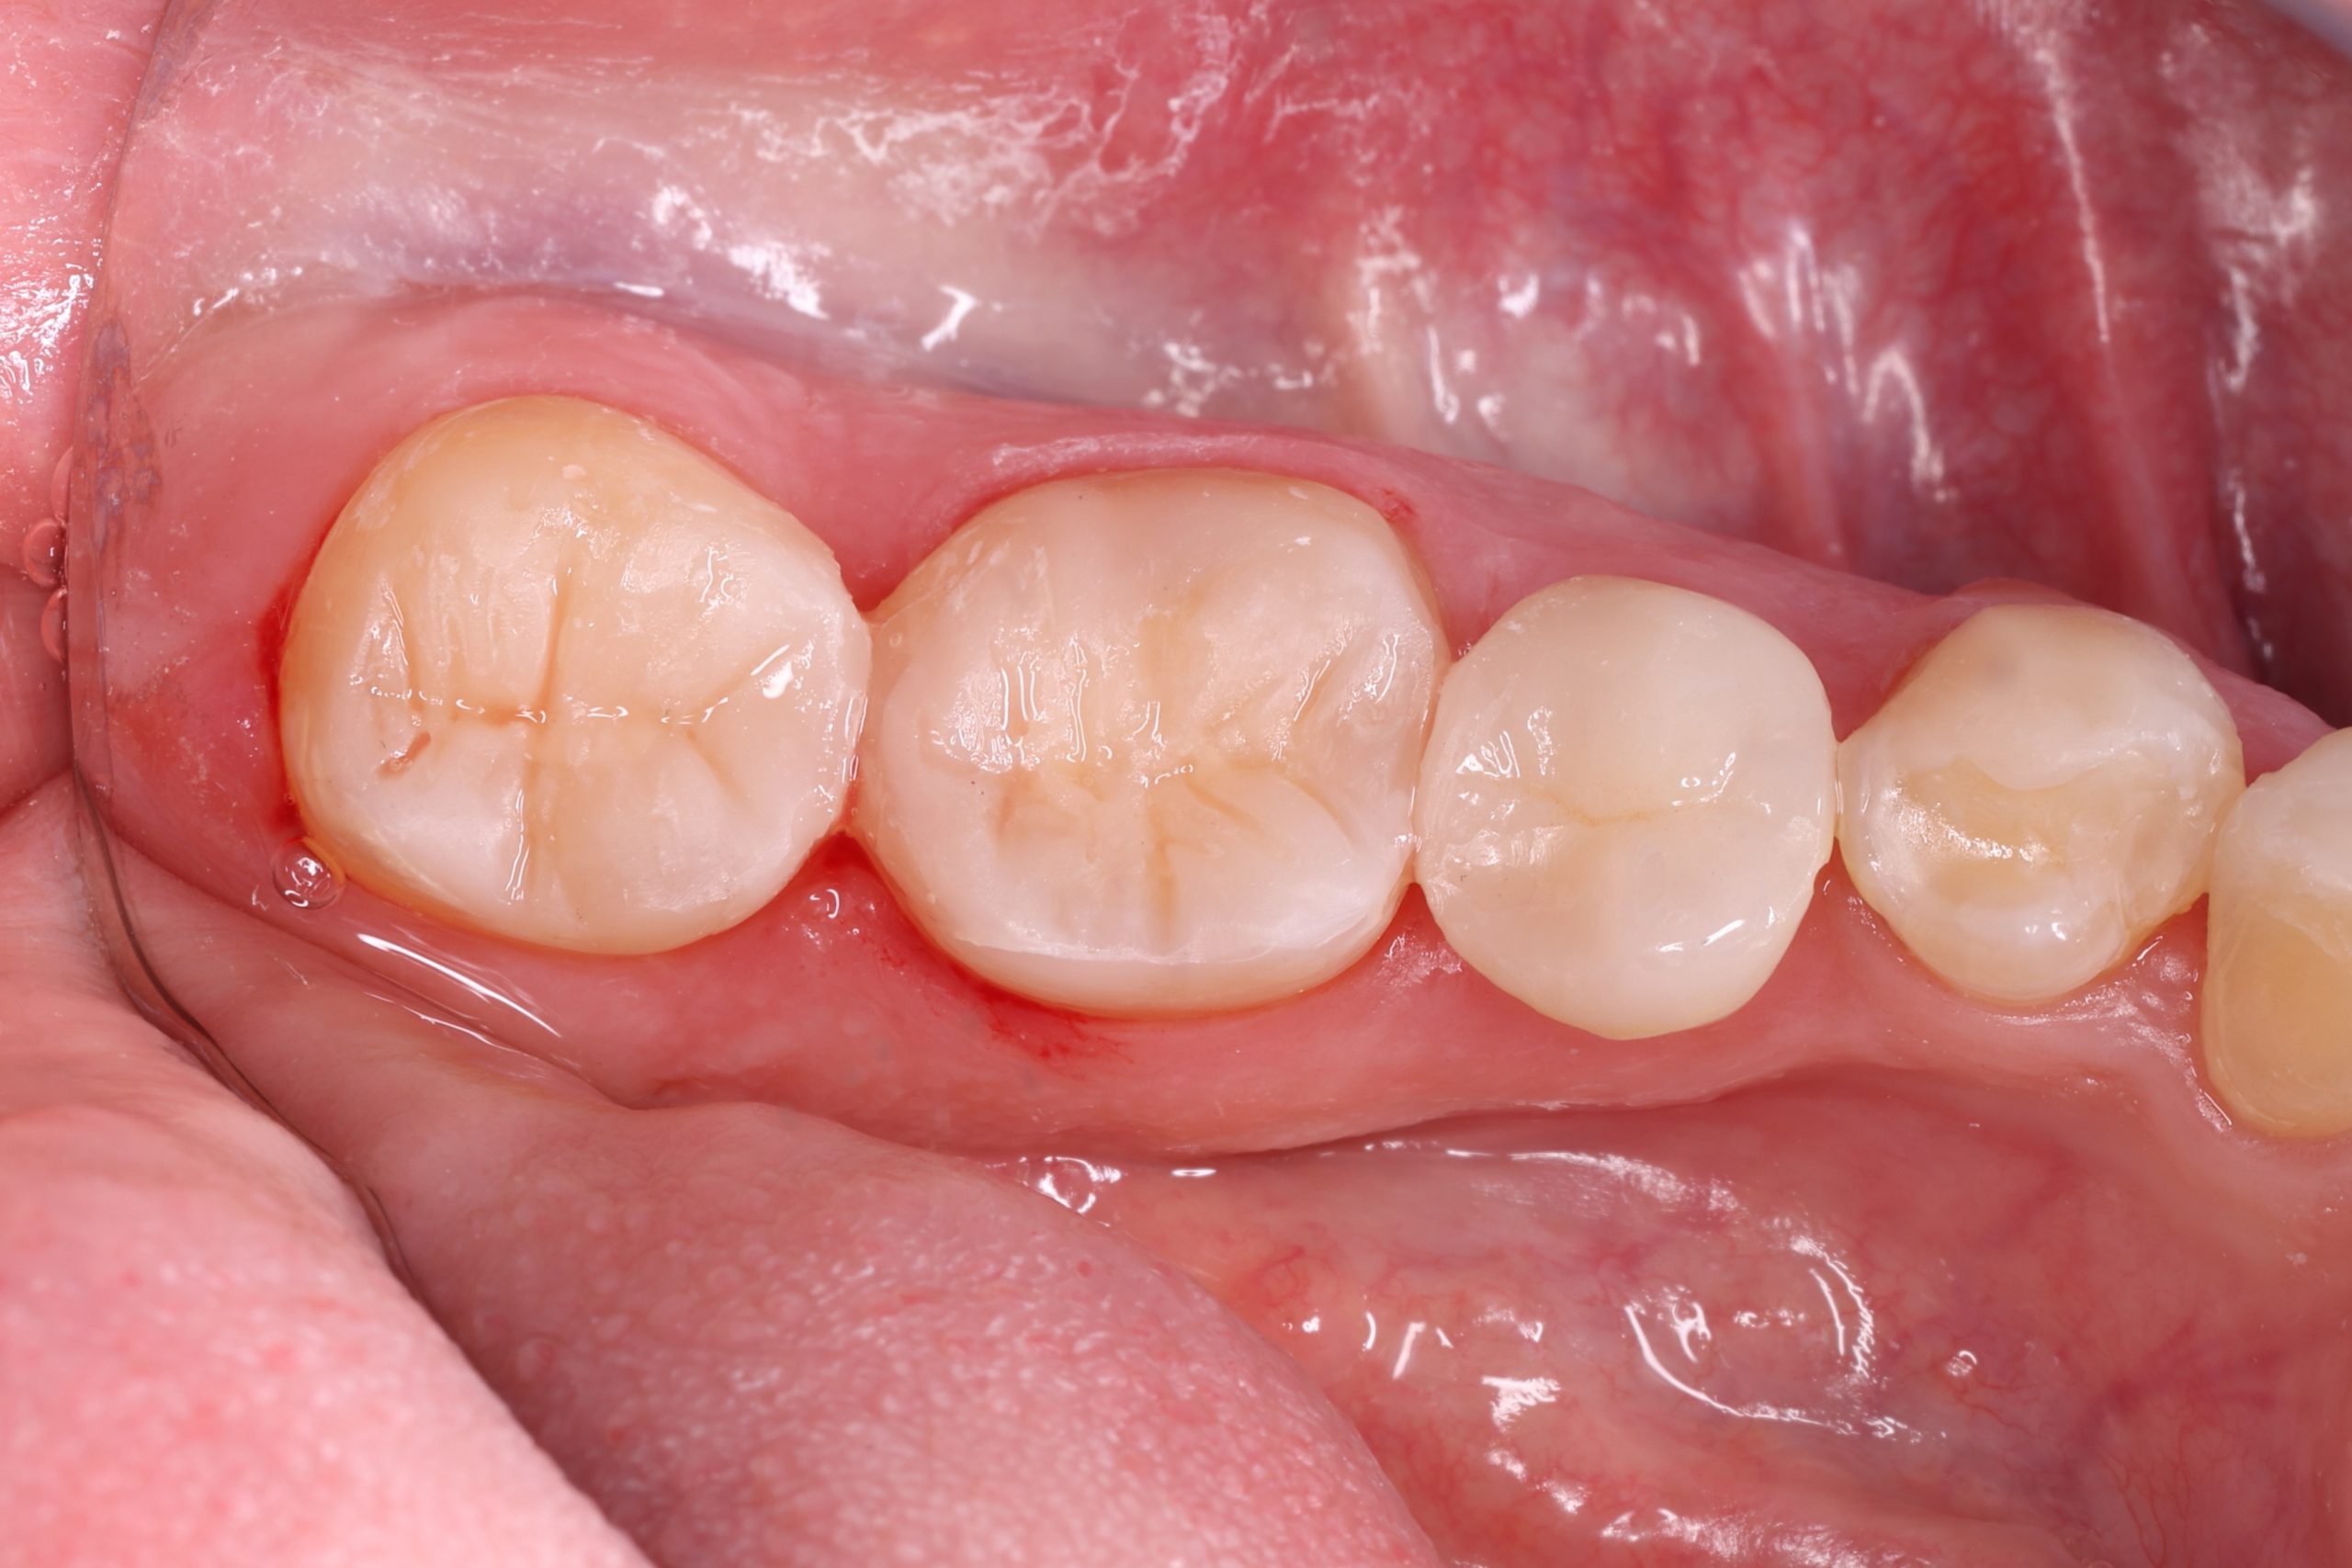

3. Layering the Composite Resin

The tooth-coloured resin is applied in thin layers and shaped carefully to match natural anatomy. For front-tooth work, we may combine several shades for a lifelike result.

5. Final Polishing and Bite Adjustment

We contour and polish the surface to a high gloss and ensure your bite feels natural in all positions.

Aesthetic and Natural-Looking

The material matches your enamel, blending into the smile with virtually invisible transitions.